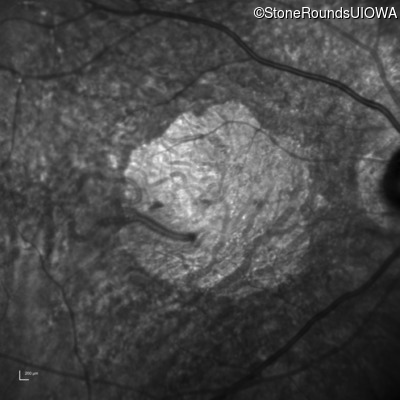

AR Stargardt Disease (IIA)

AR Stargardt Disease

ABCA4

Gly607Arg GGG>AGG

IVS30+1321 A>G

AR

Disease:

Gene:

Allele 1:

Allele 2:

Inheritance: